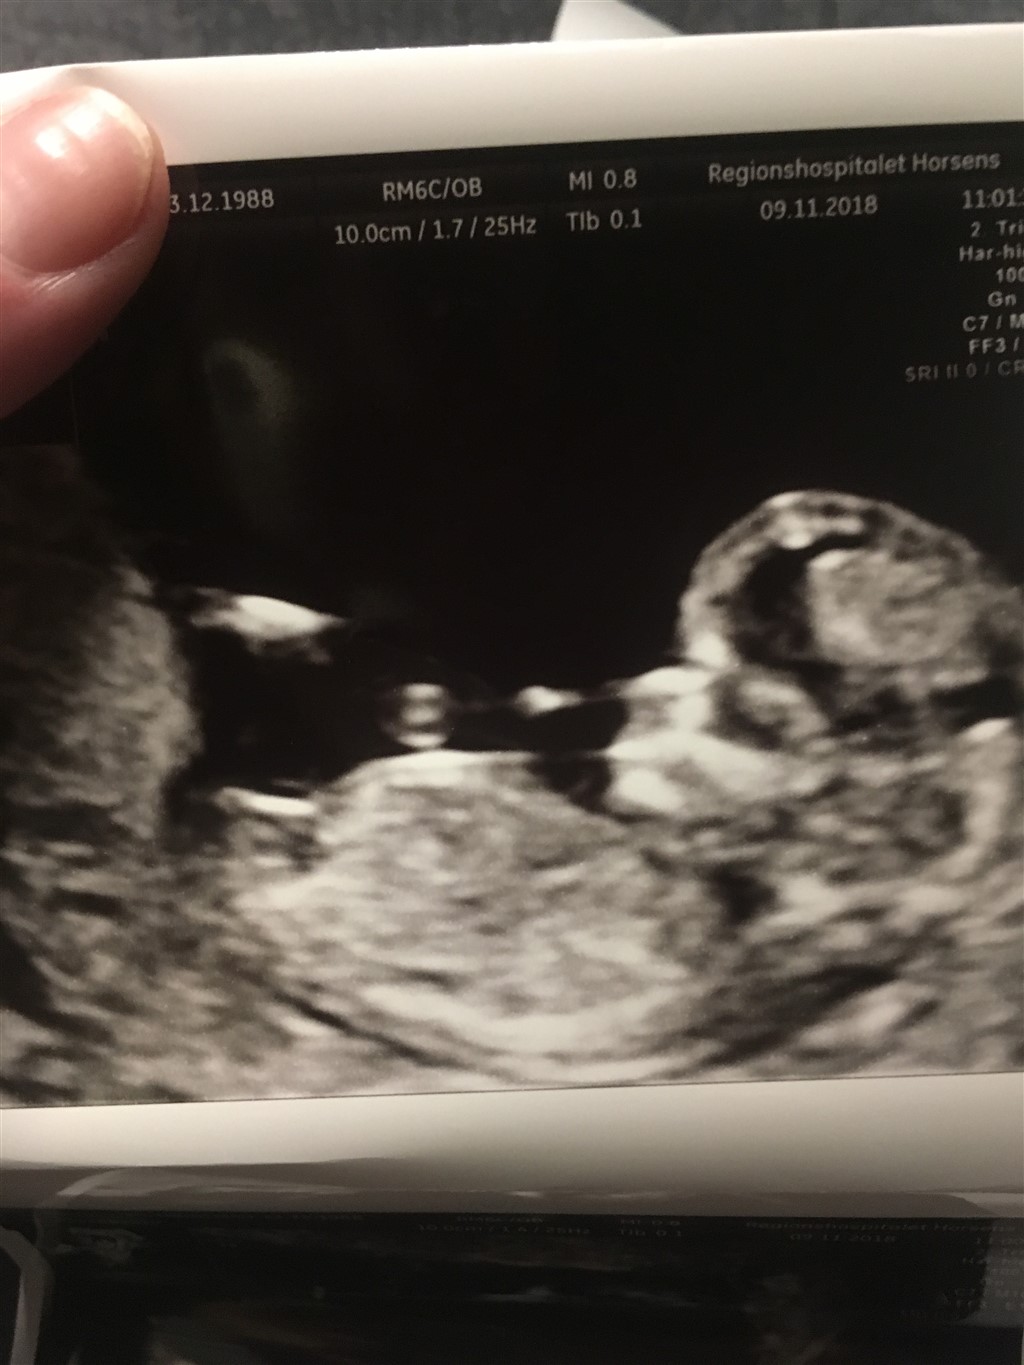

Okay, jeg har fået afvide at man ikke kan skelne med drenge og piger før uge 14+0 da de ligner hinanden dernede. Pigernes skamlæber er hævet så det ligner en drengs kønsdel. Blot til info. Det har jeg i hvertfald fået afvide igennem alle mine 3 graviditeter

Det er forkert info du har fået der. Det er rigtig at pigens skamlæber er hævede. Men tappen som udgør penis/klitoris kan fortælle jordmoder hvad køn det er.

Det sker bare yderst sjældent at en jordmoder vil fortælle så tidligt da det stadig kun er et gæt.

Efter uge 14 er det korrekt at det er nemmere at se men stadig kun et gæt